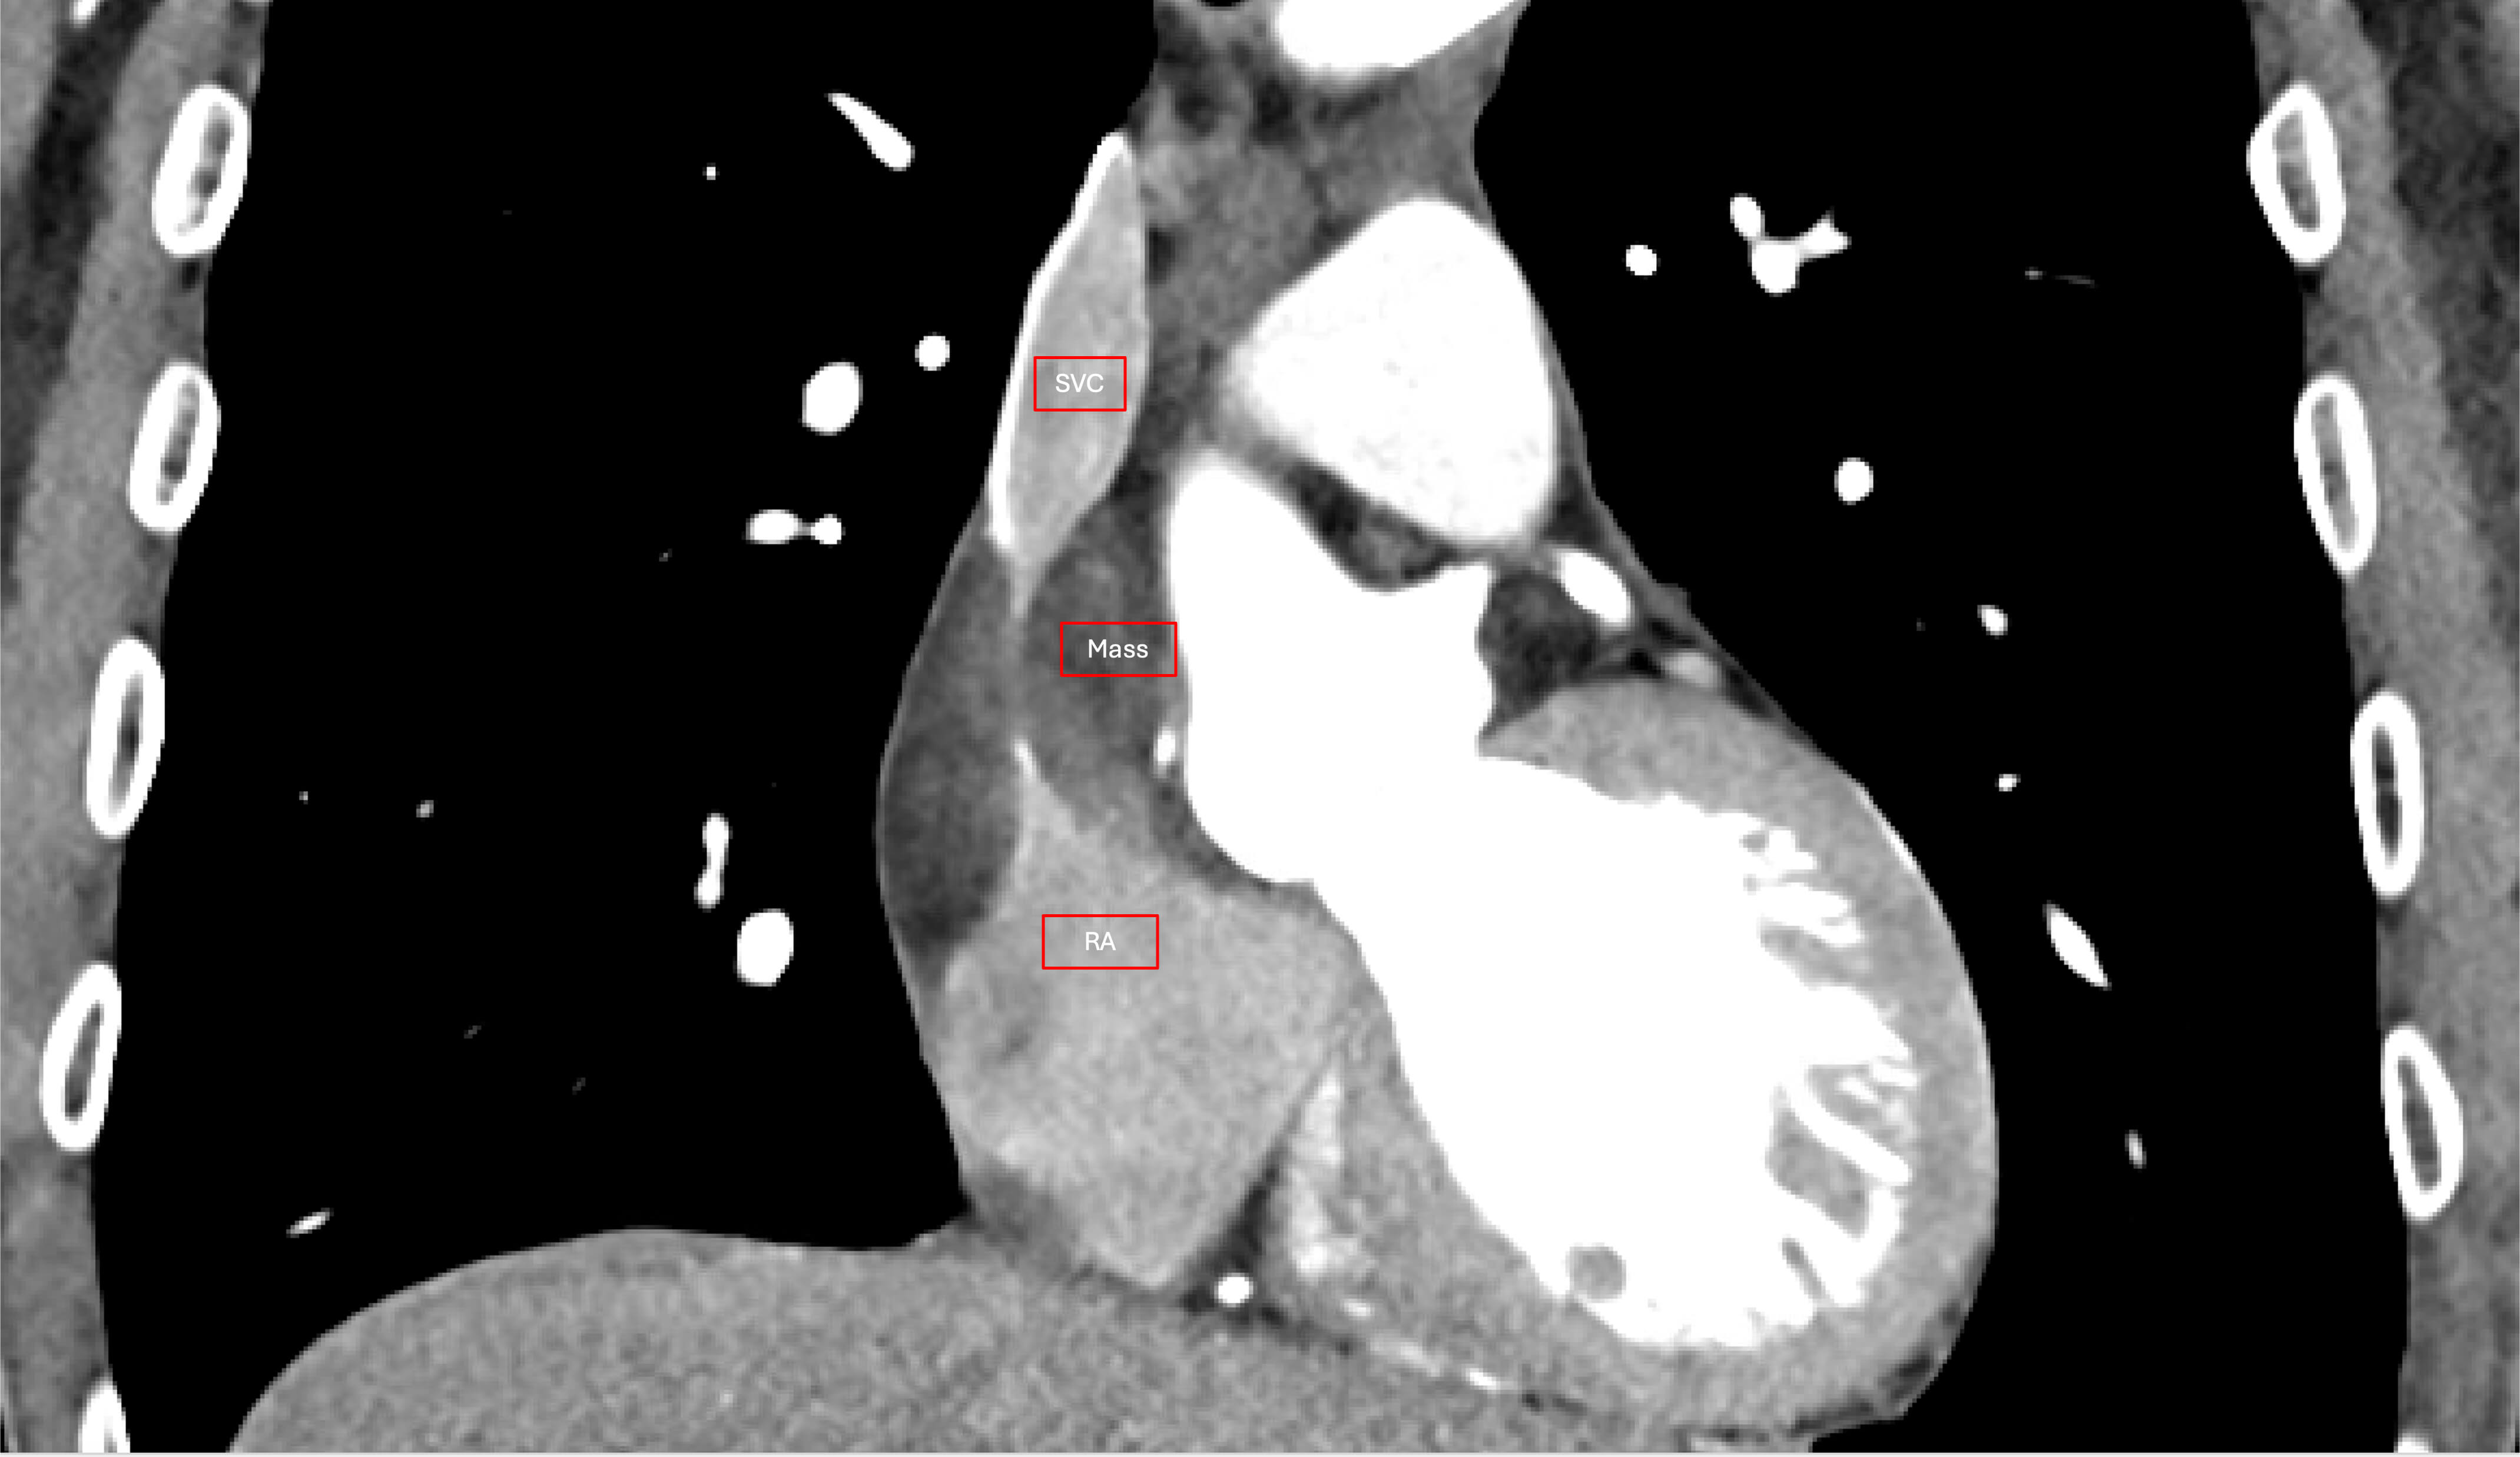

At this point, he was referred for outpatient evaluation by Cardiac Surgery. Additional workup was completed, consisting of a computed tomography angiogram (CTA) and a transesophageal echocardiogram (TEE). CTA revealed the known lipomatous mass at the level of the right atrium and interatrial septum. It measured approximately 5 cm by 4 cm and was associated with severe stenosis of the SVC at the level of the cavoatrial junction (Fig. 1). Coronary protocol CTA was suggestive of coronary artery disease, which was subsequently excluded by left heart catheterization. Notably, his cardiac catheterization revealed a prominent vessel feeding into the mass at the level of the cavoatrial junction. TEE confirmed the mass as described on CTA, with otherwise unremarkable findings; normal biventricular and valve function, no wall motion abnormalities and no intracardiac shunts. Magnetic resonance imaging (MRI) suggested lipomatous characteristics of the mass.

Fig. 1.

Computed tomography angiogram demonstrating the mass compressing the cavoatrial junction. SVC, superior vena cava; RA, right atrium.